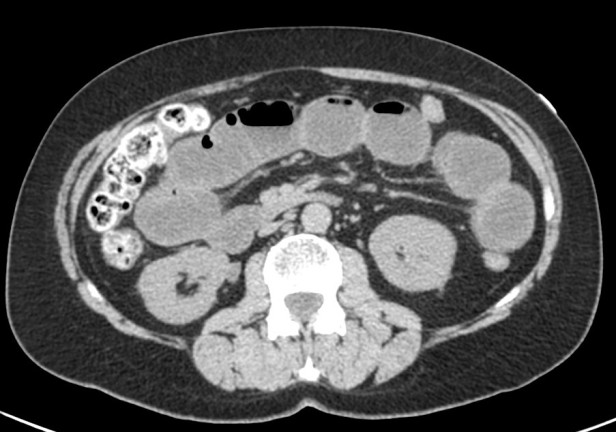

Lipoma intestinal: frecuente como punto guía o cabeza de invaginación en el instestino delgado. Aquí presentamos un caso de lipoma intraluminal en el colon, que producia obstrucción y cambios inflamatorios en el colon ascendente.